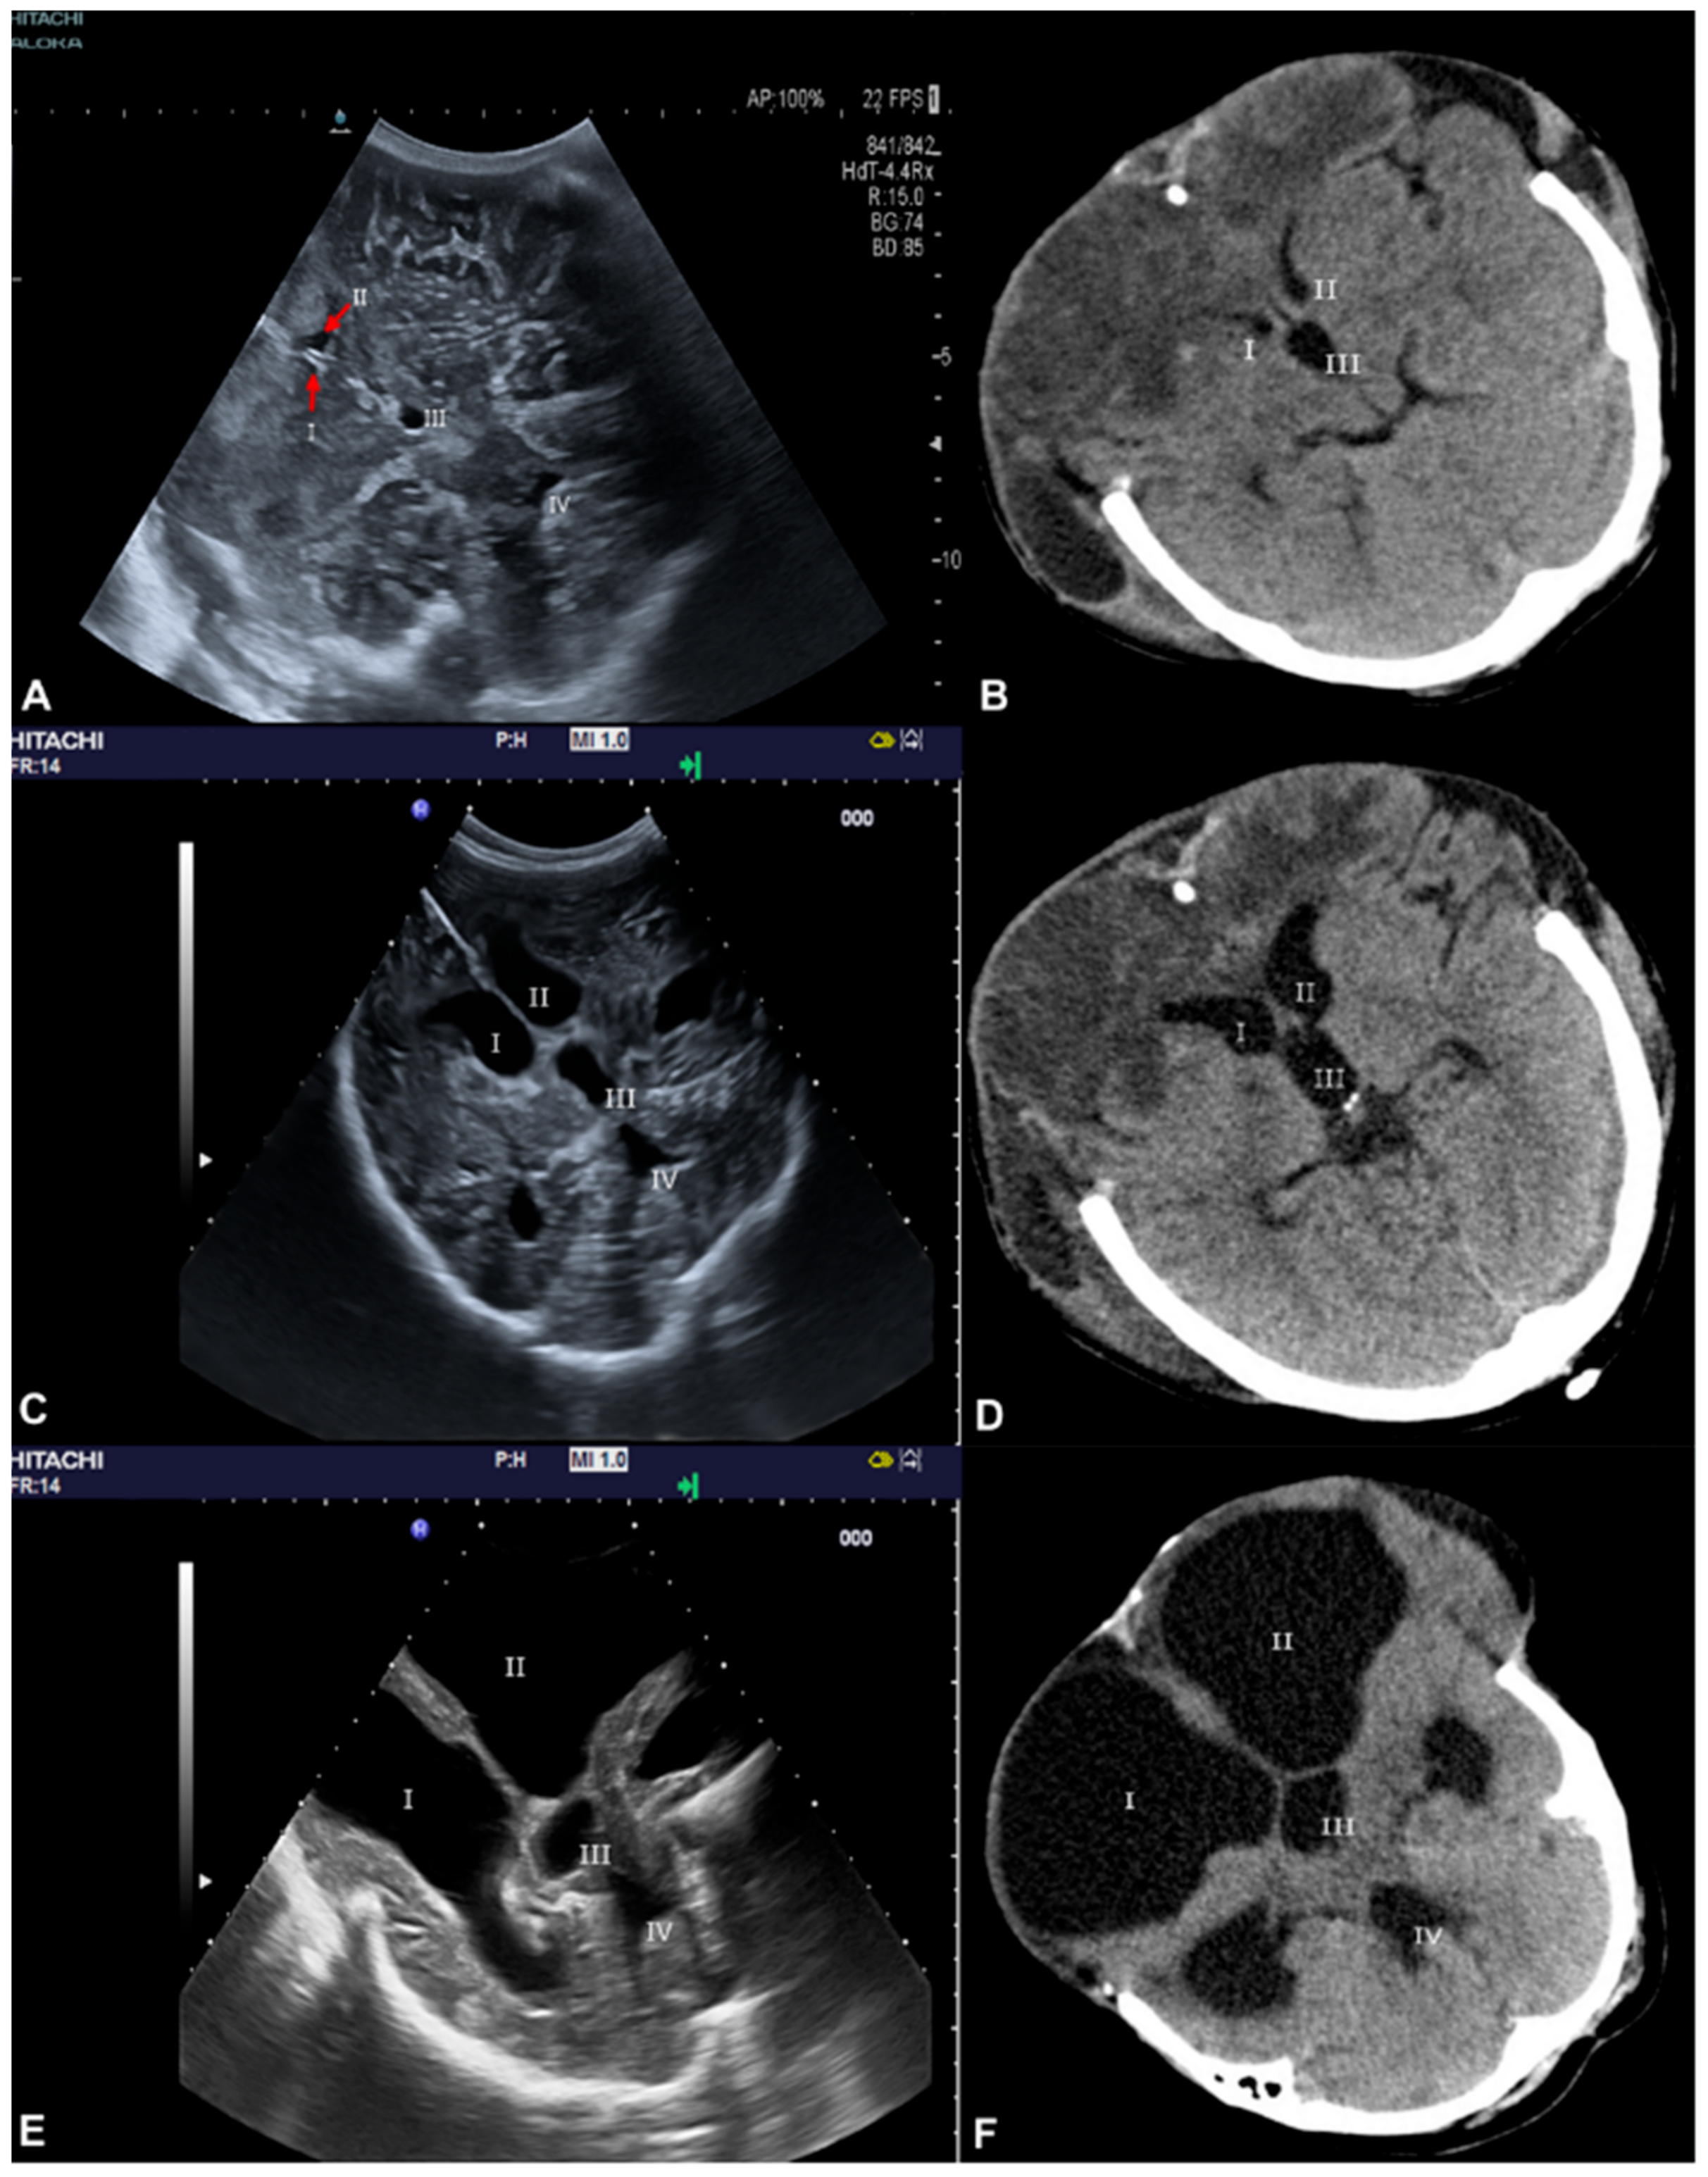

3.1. Ventricle Assessment